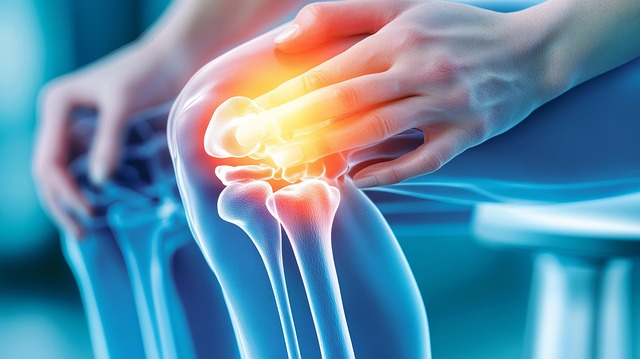

고관절은 걷기, 뛰기, 앉기 등 거의 모든 움직임에 관여하며 체중을 직접 지탱합니다. 연골 손상, 근육 불균형, 점액낭 염증, 과사용 등이 주요 원인입니다. 고관절 내부는 연골·관절막·Labrum·근육·힘줄이 밀집되어 있어, 어디가 문제인지에 따라 고관절 통증 증상이 달라집니다. 사타구니 당김은 내부 구조 문제, 옆쪽 통증은 점액낭 문제, 찝힘은 충돌증후군과 관련 있을 가능성이 높습니다.

3. 질환별 고관절 증상 비교표

| 고관절 점액낭염 | 엉덩이 옆쪽 | 눌렀을 때 통증 증가 |

| FAI 충돌증후군 | 사타구니 | 굽힘·내회전 시 찝힘 |

| Labrum 파열 | 사타구니, 소리 | 젊은 층 많음 |

| 퇴행성 고관절염 | 전반적 | 아침 뻣뻣함, 보행 통증 |

| 외측 통증 증후군 | 허리~엉덩이 | 코어 약화 관련 |